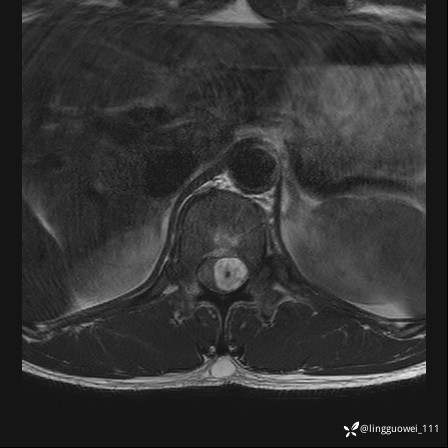

男,38岁,反复腰痛伴双腹股沟区痹痛半年,加重1月。

腰椎MR,注意脊髓异常信号,与伪影鉴别,一不小心就会漏诊

T2WI T2WI+FS